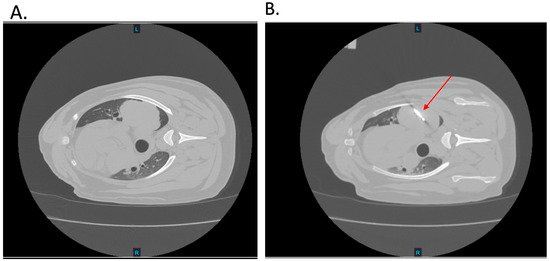

3.2.2. H-FIRE Ablation

3.3.2. Gross and Histological Outcomes of Percutaneous H-FIRE Ablation